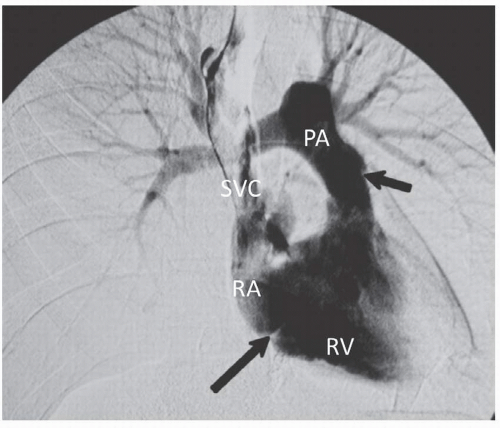

Anatomie angiographie des artères pulmonaires

Face